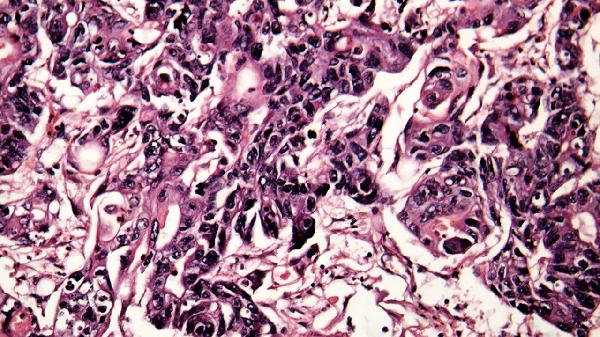

病变主要累及乙状结肠和直肠。早期肠黏膜淋巴滤泡增生形成隆起,随后中心坏死脱落形成不规则溃疡,直径多小于1厘米。溃疡间黏膜呈现弥漫性充血,显微镜下可见中性粒细胞浸润及隐窝脓肿。